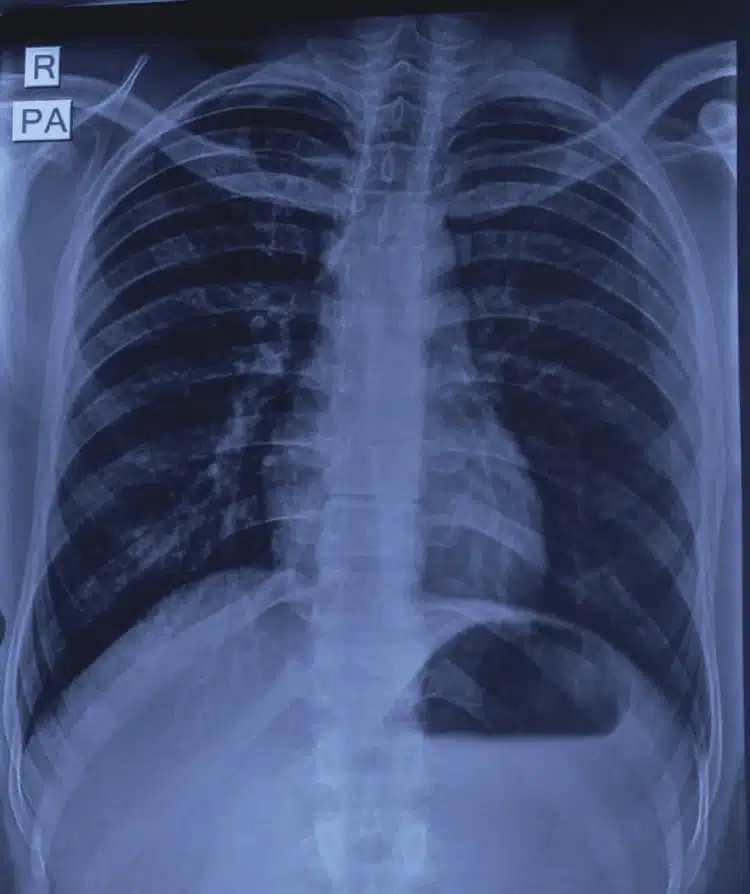

Sudah berulang kali mengeluarkannya sendiri namun gagal, tukang paip akhirnya terpaksa dipanggil untuk memotong besipaip berkenaan. Pemuda itu kemudiannya dikejarkan ke hospital untuk rawatan lanjut sebelum doktor menjalankan prosedur X-ray bagi mengesan kedudukan sebenar bidet yang sudah termasuk sehingga ke bahagian rektum (hujung usus besar).